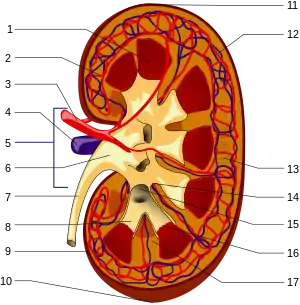

The functional substance, or parenchyma, of the human kidney is divided into two major structures: the outer renal cortex and the inner renal medulla. Grossly, these structures take the shape of eight to 18 cone-shaped renal lobes, each containing renal cortex surrounding a portion of medulla called a renal pyramid.[18] Between the renal pyramids are projections of cortex called renal columns. Nephrons, the urine-producing functional structures of the kidney, span the cortex and medulla. The initial filtering portion of a nephron is the renal corpuscle, which is located in the cortex. This is followed by a renal tubule that passes from the cortex deep into the medullary pyramids. Part of the renal cortex, a medullary ray is a collection of renal tubules that drain into a single collecting duct.

The tip, or papilla, of each pyramid empties urine into a minor calyx; minor calyces empty into major calyces, and major calyces empty into the renal pelvis. This becomes the ureter. At the hilum, the ureter and renal vein exit the kidney and the renal artery enters. Hilar fat and lymphatic tissue with lymph nodes surround these structures. The hilar fat is contiguous with a fat-filled cavity called the renal sinus. The renal sinus collectively contains the renal pelvis and calyces and separates these structures from the renal medullary tissue.[19]